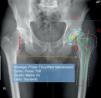

Cuarto pasoSe mide el offset femoral horizontal (distancia desde centro de rotación de la cadera hasta eje anatómico femoral) de la cadera sana. A continuación el programa solicita que se coloque un eje de simetría en el centro de la pelvis, con el fin de extrapolar (de forma automática) las mediciones realizadas en la cadera sana hacia la cadera enferma. Este paso precisa de un ajuste manual final por parte del usuario con el fin de que las referencias se sitúen exactamente sobre la punta del trocánter mayor y en el centro del canal medular femoral de la cadera enferma (fig. 1).

Una vez calibrada la magnificación de la radiografía, se extrapolan los datos de la cadera sana a la cadera a operar. Medición del offset femoral horizontal (distancia desde centro de rotación de la cadera hasta eje anatómico femoral) de la cadera sana (cadera derecha en la figura). Extrapolación hacia la cadera enferma (cadera izquierda en la figura). Este paso precisa de un ajuste manual final por parte del usuario con el fin de que las referencias se sitúen exactamente sobre la punta del trocánter mayor y en el centro del canal medular femoral de la cadera enferma.